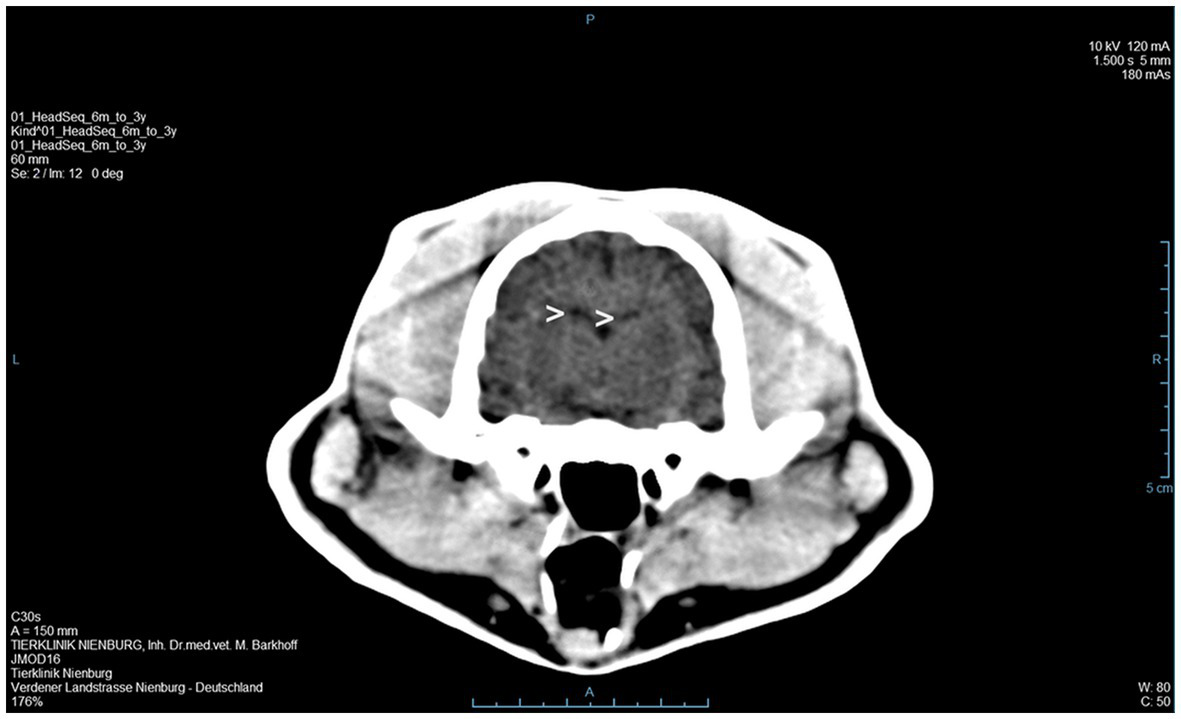

Figure 2

A computer tomographic (CT) scan of the brain revealed a dorsally broadened liquid-filled subarachnoid space as well as multifocal hypodense areas within the parenchyma. Additionally, a decreased ventricular diameter was suspected (>).

A 3 year old, male, free ranging Eurasian lynx (Lynx lynx) was found in an urban area in Hesse (Taunus) lacking escape reflexes, even when approached by humans. The animal was brought to a wildlife rescue and conservation center for observation. Clinically, the lynx was atactic (see Supplementary Videos 1, 2), with a broad based stand of the front limbs and crossed hind limbs (Figure 1). Furthermore, he showed apathy and a flea infestation. An X-ray investigation as well as a blood examination displayed no further abnormalities. In addition, the animal was tested for different infectious agents. ELISAs detecting feline leukemia virus (FeLV) antigen as well as feline immunodeficiency virus (FIV) and feline coronavirus (FCoV) antibodies were negative. IgG-antibodies against Toxoplasma gondii could be detected by an indirect immunofluorescence test (Titer: >1:1,024). The lynx was brought to an animal clinic for sampling of cerebrospinal fluid and a computer tomographic (CT) scan. The CT scan revealed degenerative changes in multiple localizations of the brain such as a dorsally broadened liquid-filled subarachnoid space as well as multifocal hypodense areas within the parenchyma. Furthermore, a generalized edema leading to a decreased diameter of the cerebral ventricles was suspected (Figure 2). In addition, an infection with Pantoea agglomerans was detected via microbiological cultivation of cerebrospinal fluid followed by 7 days of treatment with doxycycline. However, no clinical improvement was obtained. Due to worsening of clinical signs, the lynx was euthanized and a necropsy including histology of representative organ samples was performed. For histological investigation, tissue samples were fixed in neutral-buffered formalin (10%) and embedded in paraffin. Sections of 2–3 μm were cut and stained with hematoxylin–eosin (HE) and representative samples of the brain and the spinal cord were additionally stained with luxol fast blue—cresyl violet (LFB/CV). At necropsy no significant morphological findings were observed. Histologically, a multifocal, perivascular, lymphohistiocytic meningoencephalitis was present in cerebrum, cerebellum and brain stem (Figure 3A). In addition, a severe, multifocal dilation of myelin sheaths with multifocal spheroids and myelinophages as well as a mild, multifocal microgliosis was noticed in cerebellum and brain stem (Figure 3B). Similarly, the spinal cord multifocally displayed dilated myelin sheaths with occasional myelinophages. The demyelination was confirmed by LFB/CV staining (Figure 3C). Furthermore, the pulmonary lymph node showed a mild follicular hyperplasia, the mesenteric lymph node displayed a sinus histiocytosis and a mild lymphoid depletion of the tonsils was present. Moreover, a mild, focal, lymphohistiocytic myocarditis was noticed. Apart from agonal changes, no significant findings were observed in the lungs. An immunohistochemical investigation of affected brain regions for CDV nucleoprotein antigen was performed (Antibody: D110, Prof. Dr. Zurbriggen, University of Bern, monoclonal, mouse, 1:1,000 diluted) using the avidin-biotin-complex method with 3,3′-diaminobenzidine (DAB) as a chromogen as described elsewhere (17, 18). CDV-nucleoprotein was detected intralesionally in the gray and white matter of cerebrum and cerebellum (Figure 3D). There was no CDV nucleoprotein detectable within the spinal cord. Additionally, within myocardium, liver, lungs, representative lymph nodes, spleen and intestine CDV nucleoprotein was not detected. The CDV infection of the central nervous system was confirmed on a molecular level via reverse transcriptase polymerase chain reaction (RT-PCR) and Sanger sequencing using hemagglutinin (H) specific primers as previously described (19) using frozen CNS tissue. Analysis of the resulting H gene sequence (GenBank accession no. OR161408) showed only one non-synonymous amino acid substitution (I55T) in comparison to three Europe-1 strains which were previously identified in a fox (GenBank accession no. OL795426) and two raccoons (GenBank accession nos. MN267060 and MN267062) in Germany in 2015. Toxoplasma gondii (Antibody: Biocyc GmbH & Co. KG, Potsdam, Germany, polyclonal, rabbit, 1:75 diluted) and feline leukemia virus (Antibody: C11D8; Custom Monoclonals International Corp., Sacramento, United States, monoclonal, mouse, 1:200 diluted) antigens were not detected in the central nervous system using immunohistochemistry.

The lynx displayed a demyelinating meningoencephalitis caused by an infection with canine distemper virus. The histological lesions in the central nervous system are similar to the typical findings observed in the chronic phase of nervous distemper in dogs (3). Daoust et al. made similar observations regarding CDV manifestations in six Canadian lynx and one bobcat in Canada. Five of those animals were further investigated with RT-PCR and nucleotide sequencing and in all but one case, a CDV infection was confirmed. Affected animals of the Canadian study showed varying degrees of microgliosis and perivascular cuffing, as was also observed in the present case. While demyelination was a very prominent finding in the current study, only a subset of the lynx investigated by Daoust et al. exhibited this pathological change. In contrast to our findings, Daoust et al. also observed neuronal necrosis in most lynx (13). Regarding diagnostic imaging, the findings of the CT scan in the present case also show similarities to changes observed with magnetic resonance imaging (MRI) in CDV infected dogs. In the literature, a correlation of MRI and histological findings of demyelination in the brainstem and cerebellum was observed and MRI has been shown to be a sensitive tool for the diagnosis of demyelination (20), which might also be the case for CT scans considering the results of the present case.